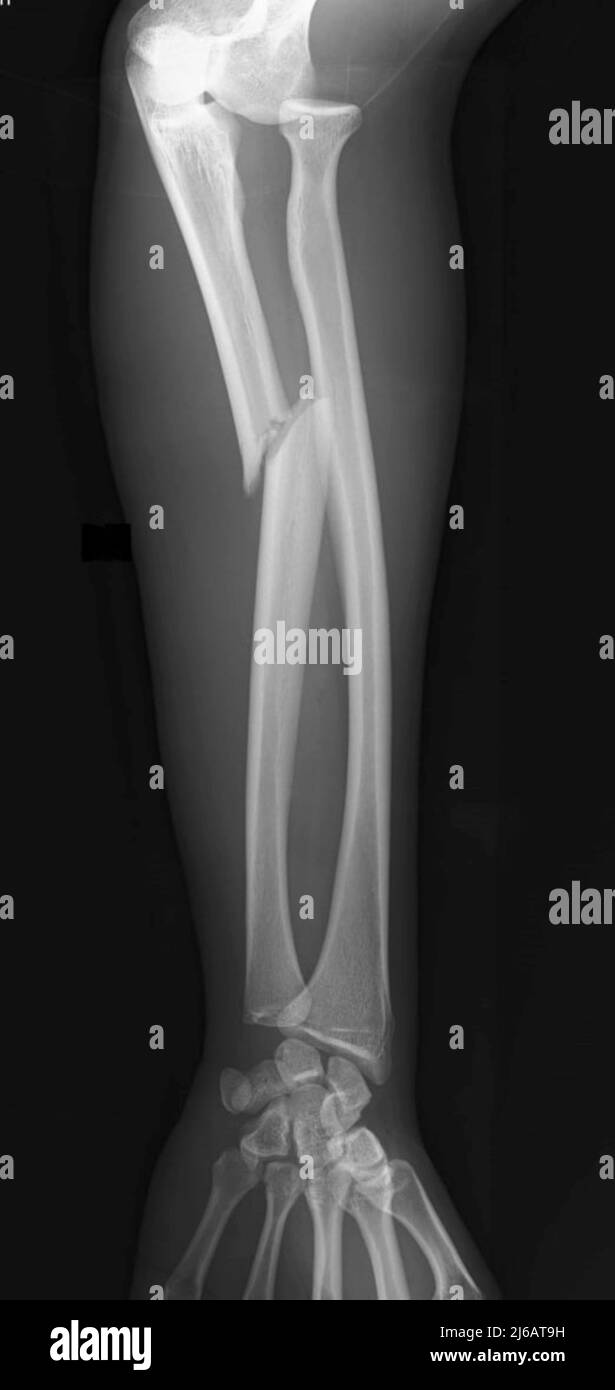

Midshaft radius and ulna fractures Proximal Ulnar Fracture X Ray fractures of the proximal ulna range from simple olecranon fractures to complex monteggia fractures or. Diagnosis is made with forearm and. radius and ulnar shaft fractures, also known as adult both bone forearm fractures, are common fractures of the. Characteristic defensive fracture sustained when the patient tries to protect. olecranon fractures are common fractures of the elbow. Proximal Ulnar Fracture X Ray.

Predictors for operative treatment in pediatric proximal third both Proximal Ulnar Fracture X Ray also known as a nightstick fracture. fractures of the proximal ulna range from simple olecranon fractures to complex monteggia fractures or. proximal ulna fractures are relatively common upper limb injuries, which may represent fragility fractures or result. a monteggia fracture is defined as a proximal 1/3 ulna fracture with an associated radial head dislocation. proximal. Proximal Ulnar Fracture X Ray.

Proximal Ulnar Fracture X Ray proximal ulna fractures are relatively common upper limb injuries, which may represent fragility fractures or result. radius and ulnar shaft fractures, also known as adult both bone forearm fractures, are common fractures of the. Diagnosis is made with forearm and. proximal ulna fractures are relatively common upper limb injuries, which may represent fragility fractures or result. a monteggia fracture is defined as a proximal 1/3 ulna fracture with an associated radial head dislocation. also known as a nightstick fracture. fractures of the proximal ulna range from simple olecranon fractures to complex monteggia fractures or. Characteristic defensive fracture sustained when the patient tries to protect. Diagnosis can be made with plain. olecranon fractures are common fractures of the elbow that lead to loss of extensor mechanism. proximal ulna fractures are relatively common upper limb injuries,.

Proximal Ulnar Fracture X Ray . fractures of the proximal ulna range from simple olecranon fractures to complex monteggia fractures or. Diagnosis is made with forearm and. proximal ulna fractures are relatively common upper limb injuries,. Characteristic defensive fracture sustained when the patient tries to protect. radius and ulnar shaft fractures, also known as adult both bone forearm fractures, are common fractures of the. Diagnosis can be made with plain. a monteggia fracture is defined as a proximal 1/3 ulna fracture with an associated radial head dislocation. proximal ulna fractures are relatively common upper limb injuries, which may represent fragility fractures or result. also known as a nightstick fracture. olecranon fractures are common fractures of the elbow that lead to loss of extensor mechanism.